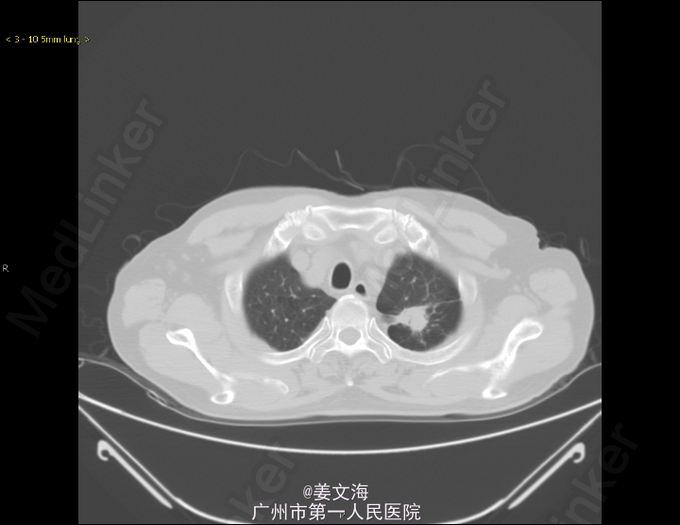

主诉:咳嗽8月余,咳血丝痰6月 病史:患者于8月前因反复咳嗽、咯血就诊于当地医院,当时胸部CT示双肺结核,左上肺真菌感染,痰结核菌培养阳性,予3HRZE/9HR方案抗结核治疗,并予伏立康唑抗真菌治疗。患者因经济原因使用伏立康唑1月后自行停药。后曾短期口服伊曲康唑胶囊。经治疗后,咳嗽减轻,仍间断咯血痰。既往史:高血压病。2007年曾患左肺结核,抗结核治疗1年。现为求进一步诊治来我院。

查体:双肺呼吸音清,未闻及干湿啰音。其余无特殊。 辅助检查: 胸部CT提示:左肺继发型肺结核并空洞形成,考虑合并真菌感染可能性大。右肺多发小结节,考虑结核增殖灶可能。 经皮肺活检病理提示:(左上肺)符合真菌感染。送检物为少量真菌菌丝,呈团状,其形态学符合曲菌。

诊断:1.左上肺真菌感染;2.双肺继发性肺结核;3.高血压病。 处理:予抗结核、先后予伊曲康唑、卡泊芬净针抗真菌、祛痰止咳、止血、降压、对症支持治疗。